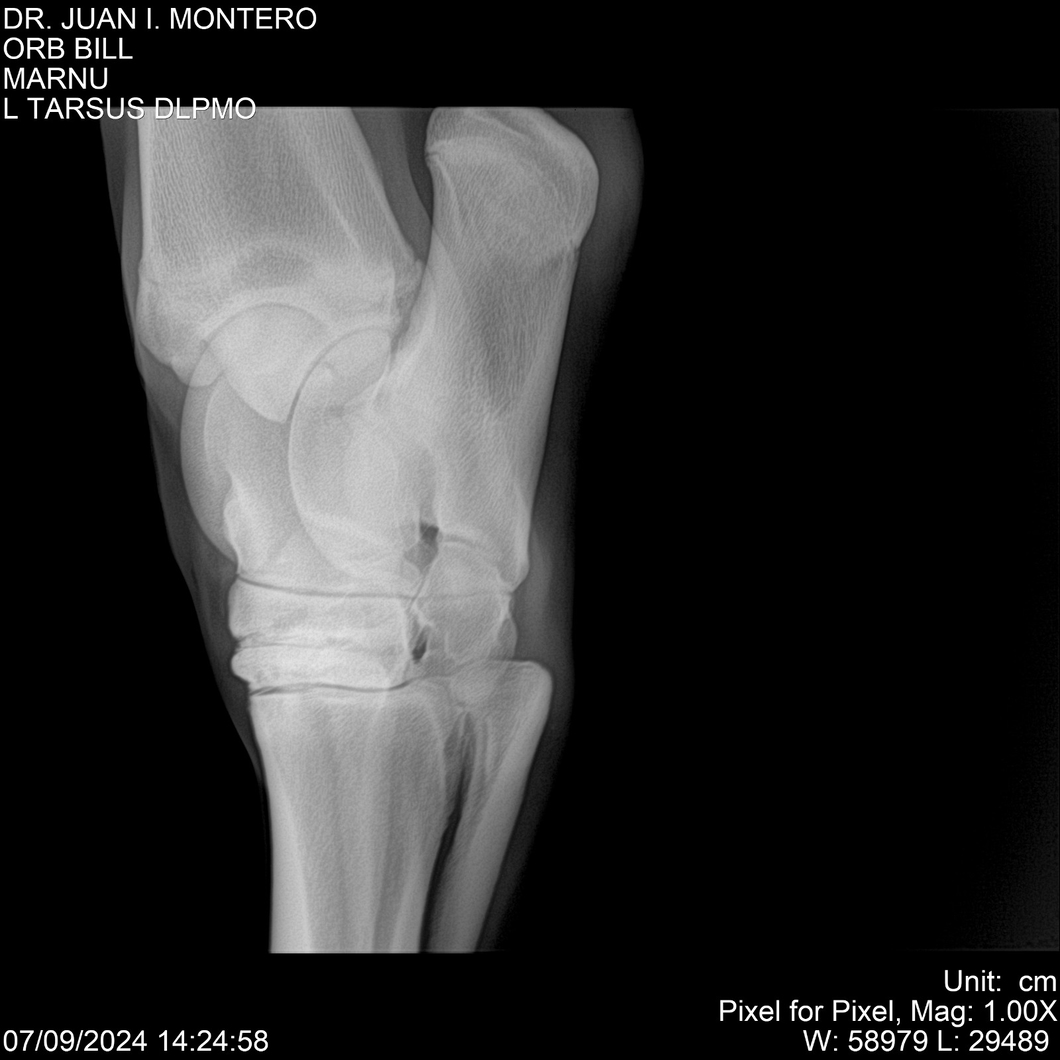

LOTE 7, ORB BILL 🔥 🔥 🔥 Lote Anterior Volver al remate Lote Siguiente Ficha Contacto Montevideo - Ficha del Lote Identificador: #282523 Categoría: Yeguarizos Montevideo - 83 Visualizaciones ClicData Contacto Empresa: Abelenda N. R., Walter Hugo Nombre*: Teléfono* : E-mail* : Mensaje Enviar Registrese gratis Este contenido Exclusivo está disponible sólo para usuarios registrados Ingresar